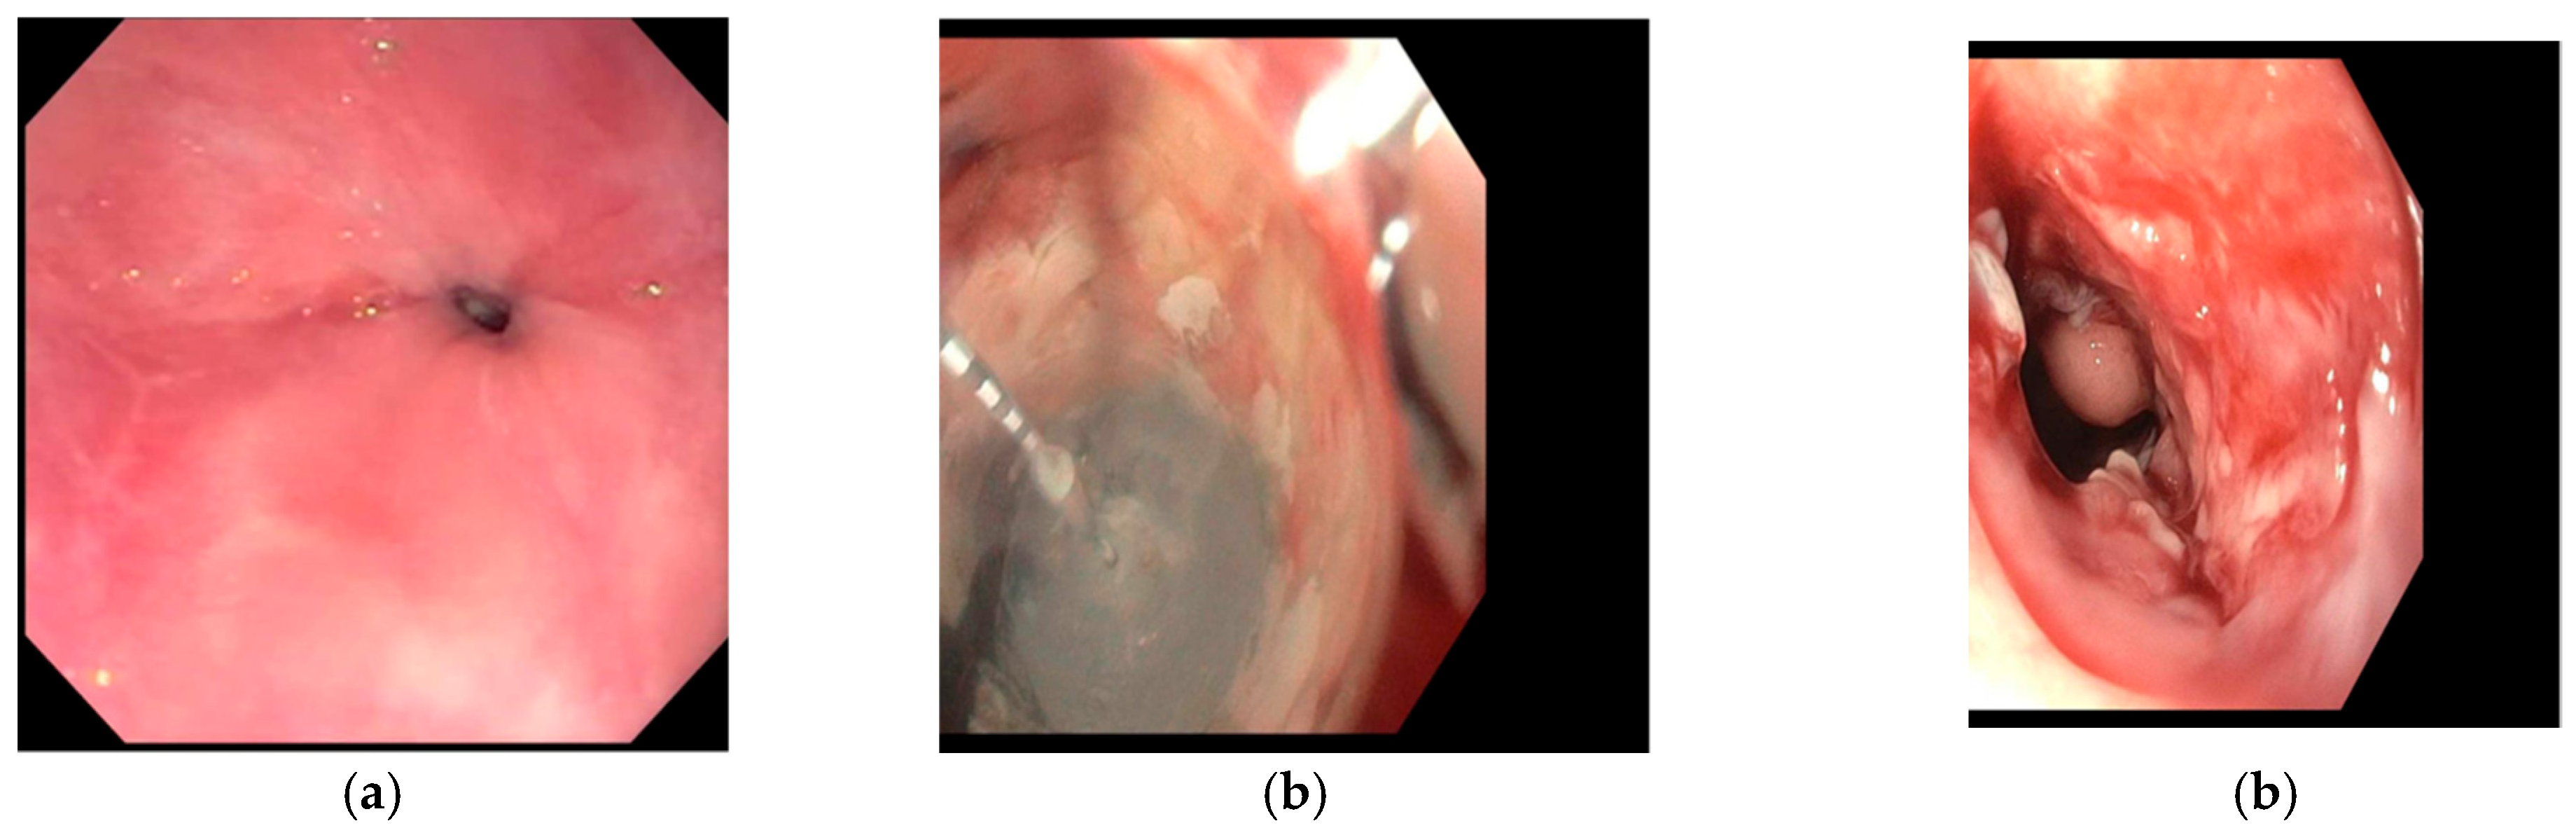

2. Evolution of Cryotherapy

4. Types of Endoscopic Cryotherapy Methods